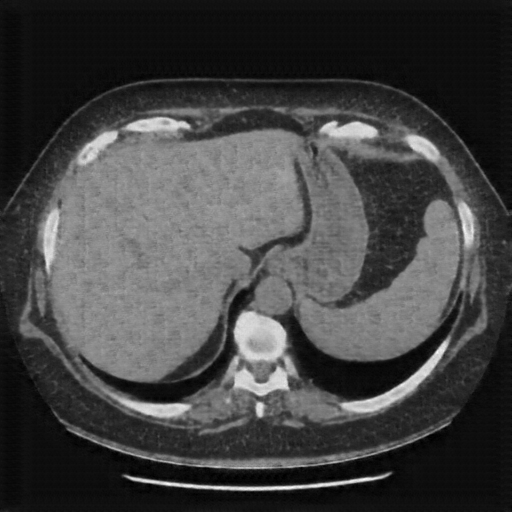

Reconstructed NATIVE CT scan (cycle consistency)

Full window (WL 1023.5, WW 4095 β†’ Low βˆ’1024, High +3071)

Actual HU range: [-1024.0, 544.7]